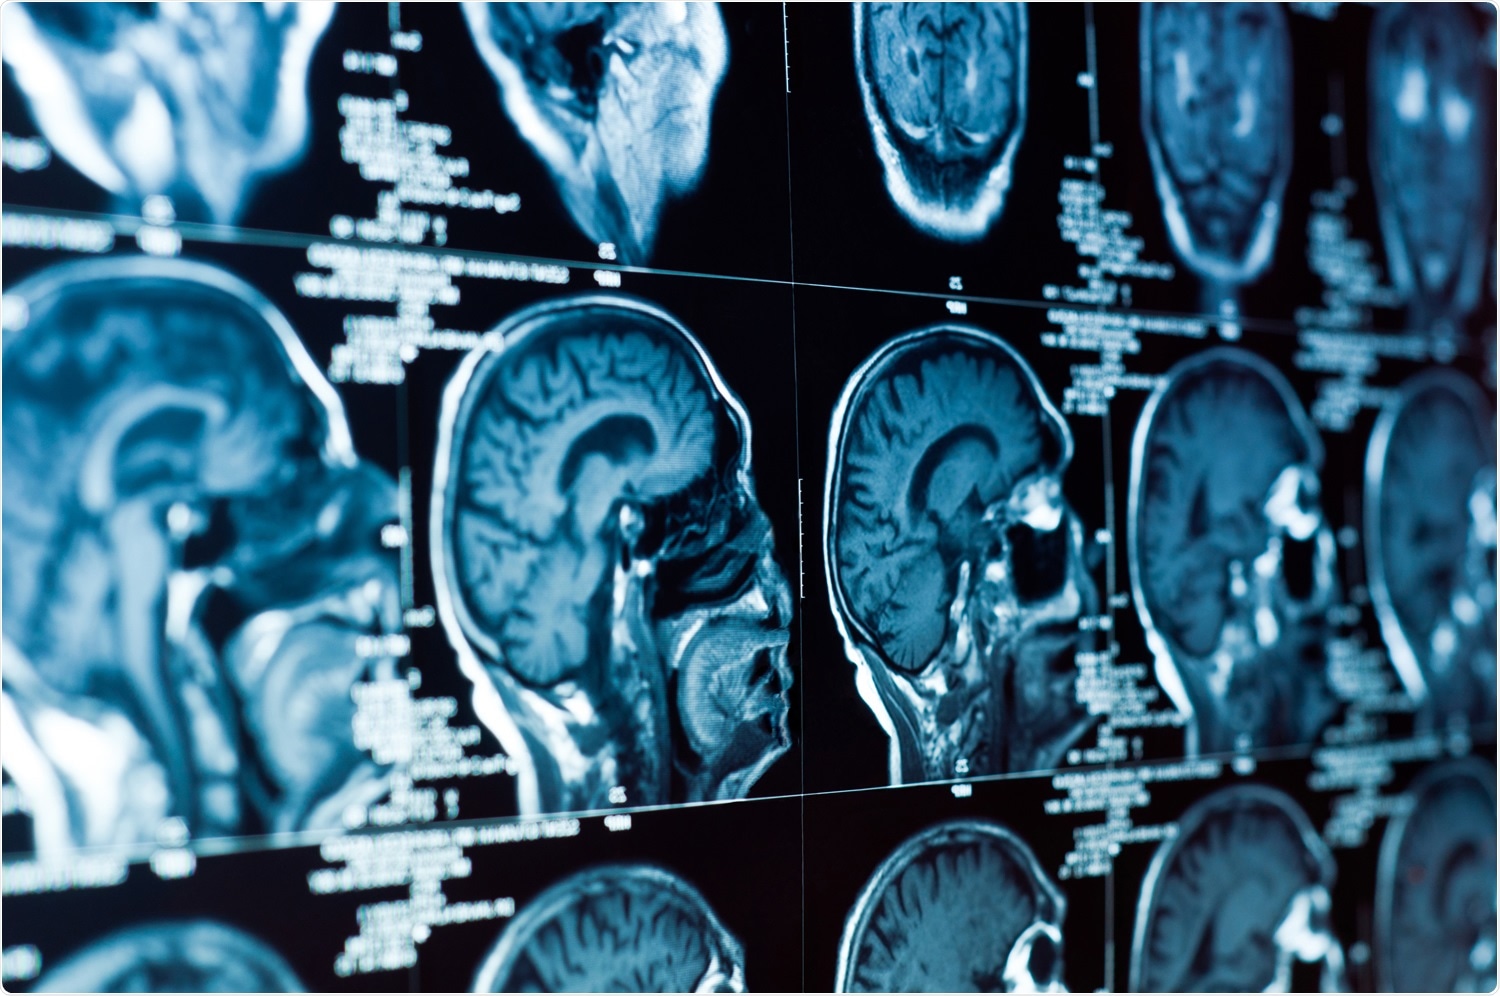

New research suggests pneumonia in COVID-19 patients is linked to viral-induced changes in the brain. MRI scans revealed 57.9% of severe acute respiratory syndrome coronavirus 2 (SARS-CoV-2) infected patients had recent brain lesions.

MRI scans showed brain lesions in 82.6% of patients. Additionally, about 57.9% of the identified brain legions were recent, suggesting the lesions were linked to SARS-CoV-2 infection. Only 41.1% of brain lesions were considered old.

Of the 57.9% with recent brain legions, 77.3% of these lesions were deemed “clinically significant.” These patients were the ones who had a stroke. Eight experienced a recent infarct, and five patients had a recent cerebral hemorrhage. In addition, four patients showed signs of global hypoxic-ischemic encephalopathy.